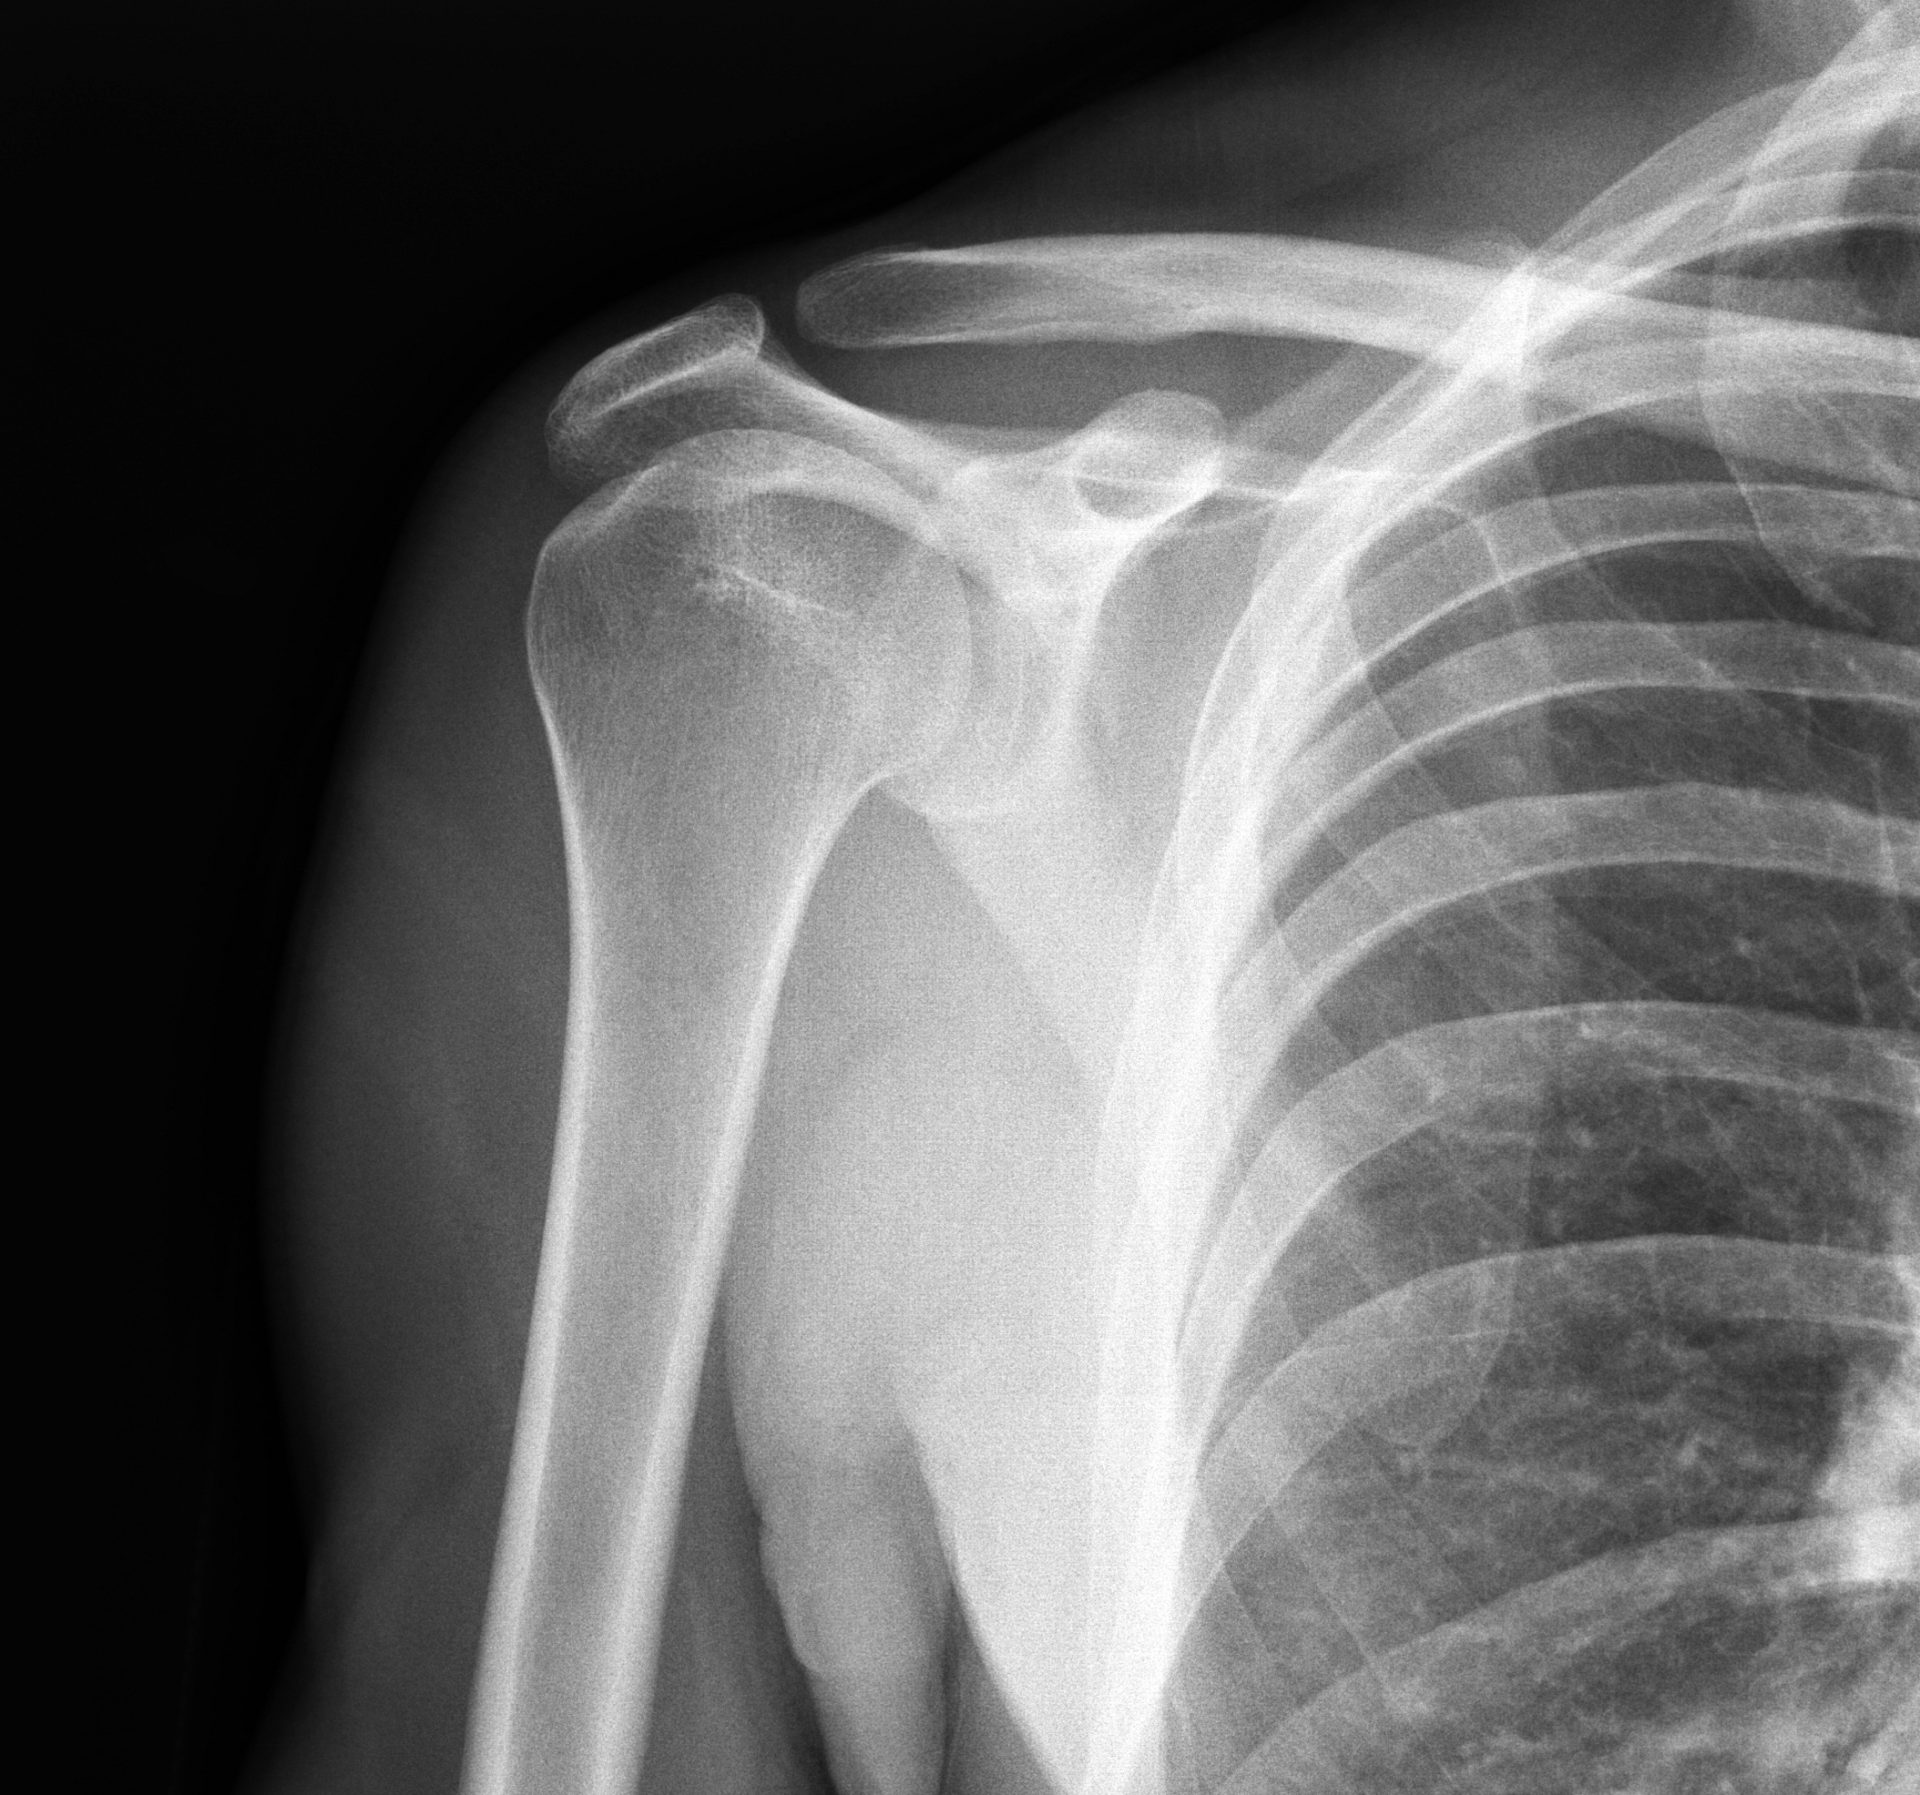

Xray of shoulder joint. Irvings Law